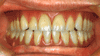

インプラント治療完了後。美しい仕上がりです。![]() ![]() |

| 1.術前の骨欠損状態 | 2.ディストラクション終了後、ディストラクションフィクスチャーを除去し、インプラント2本を埋入 |

| 3.ディストラクションフィクスチャーの埋入 | 4.垂直性骨増大と角質化した歯肉の術後の状態 |